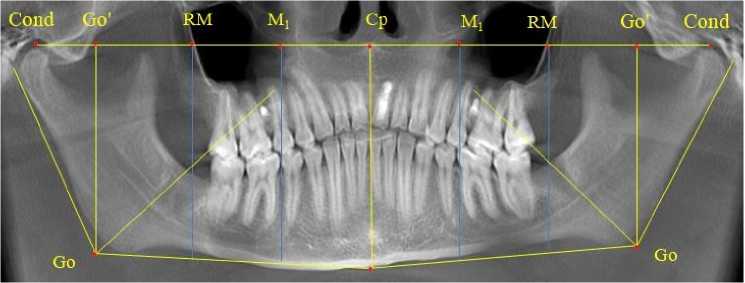

На ортопантомограммах устанавливались точки и линии, позволяющие оценить размеры зубоальвеолярных дуг и оптимальное положение дистально расположенных в окклюзии зубов. С этой целью на верхнюю точку суставной головки, с обеих сторон, устанавливали точки кон-дилион ( Сond ), которые соединяли суставной горизонталью. От середины суставной горизонтали проводили срединную вертикаль, которая, как правило, соединяла центральную (срединную) точку ( Ср ) с подбородочной точкой Ме .

Конструируемая точка гонион ( Go ) определялась традиционно при пересечении касательной линии к ветви челюсти с линией, соединяющей точку Go с нижней подбородочной точкой ментос ( Ме ), расположенной в нижней части подбородка по средней линии. От угловой точки Go строили перпендикуляр к горизонтальной суставной линии. На месте пересечения линий устанавливали точку Go ´. Предложенное построение обусловлено тем, что на ортопантомограмме, в отличие от телерентгенограммы, величина нижнечелюстного угла может быть искажена.

Расстояние между точками Go ´ и центральной точкой ( Central point ) Ср делили на коэффициент 1,5. Полученную расчетную величину откладывали от центральной точки на суставную горизонталь с обозначением точки (RM), от которой опускали перпендикуляр, который располагался в ретромолярной зоне и, как правило, проходил вблизи дистальных поверхностей задних зубов, ограничивающих зубоальвеолярные дуги. Кроме того, половина расстояния Ср-RM определяло положение молярной вертикали и точку на суставной горизонтали обозначали как М 1 (рис. 1).

Рис. 1. Анализ ортопантомограммы ребенка в периоде сменного прикуса при определении положения дистально расположенных зубов

Результаты анализа ортопантомограмм детей в периоде сформированного прикуса молочных зубов показали особенности расположения зачатков постоянных замещающих зубов по отношению к корням молочных зубов и формирование зачатков добавочных зубов, к которым относились дистально расположенные моляры постоянного прикуса.

Линия эстетического центра проходила от середины межсуставной горизонтали ( Cond-Cond ) и перпендикулярно к ней. Указанный ориентир проходил между медиальными резцами обеих челюстей до нижнего края подбородка (точка Ме).

Отношение отрезка суставной горизонтали от центральной точки (Ср) до проекции гонио-нальной точки (Go´) к коэффициенту 1,5 определяло расположение отправного точечного ориентира (RM) для построения ретромолярной вертикали перпендикулярно к суставной горизонтали. Особенностью исследуемого возрастного периода было то, что зачаток первого верхнего постоянного моляра при оптимальном окклюзионном соотношении располагался впереди ретромолярной вертикали. Данное обстоятельство свидетельствовало о благоприятном расположении зачатка, что в последующем обеспечивало его прорезывание по мере формирования корней. Кроме того, указанный размер (Ср-RM) определял зубоальвеолярный размер верхней челюсти (правой и левой). Молярная вертикаль, исходящая из молярной токи (М1), проходила через дистальные поверхности первых молочных моляров обеих челюстей (рис. 3).

Рис. 3. Анализ ортопантомограммы ребенка 4 лет в периоде прикуса молочных зубов

Зачатки первых постоянных моляров нижней челюсти располагались кпереди по отношению к биссектрисе угла Go´-Go-Ме , что так же, как и на верхней челюсти, оказывало благоприятное влияние на формирование и прорезывание нижнего первого моляра. Антимеры обеих челюстей располагались симметрично относительно диагностических линий.